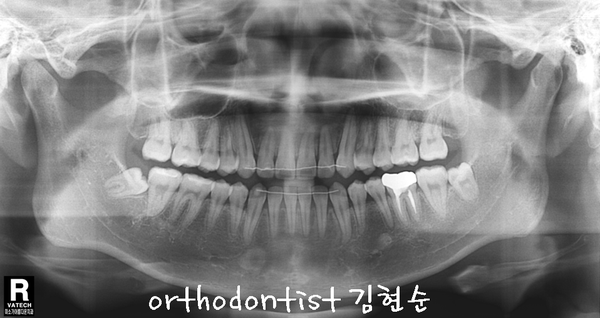

반대 교합 -

교정 문의 환자 : 김 0 0

나이 : 24 세 F / 환자분 소개

교정 사유 : 반대 교합 / 치아 중심선 / 주걱턱

아래 환자분의 증례를 통해 알아보겠습니다

- 일단 치열이 고르지 못합니다 사이사이 공간도 벌어져 보입니다 ..

- 아래 치아가 윗니보다 나와 보이고 턱도 돌출 모습을 보이고 있습니다

- 정면에선 치아 중심선, 가운데 라인이 맞지 않습니다

- 흔히 말하는 반대 교합을 보이고 있습니다

- 중간중간 벌어짐과 틈새가 보입니다

- 위/아래 사진으로 옆모습 벌어진 간격이 넓습니다;;...

- E - LINE 보면 아래턱과 입술이 돌출된 모습을 확인할 수 있습니다

Treatment plan

이상적으로는 아래턱 돌출 개선을 위한 교정 + 턱 수술 필요, 교정만으로는 턱 돌출 개선 어려움

아래 치아 공간 모아서 앞니 관계 개선을 위한 비발치 교정 치료

상하 교정 장치 부착 → 치아 배열 → 아래 치아 사이 공간 모음 & 고무줄

예상 교정 기간 약 12 개월